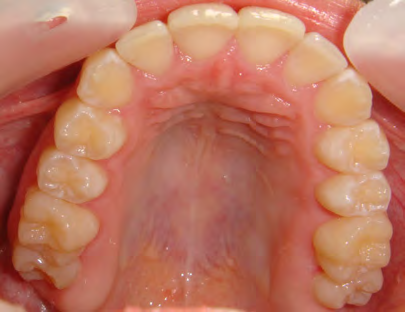

All of the patients below had been told they required extractions by orthodontists, some insisting that they could not be treated without extractions.

They were all treated without extractions, head gear or facemasks at Vakresmil and represent just a small sample of cases treated between 2004–2014.

The patient below had severe crowding of both upper canines and the lower right 5. The upper 4’s and 2’s were actually in contact.